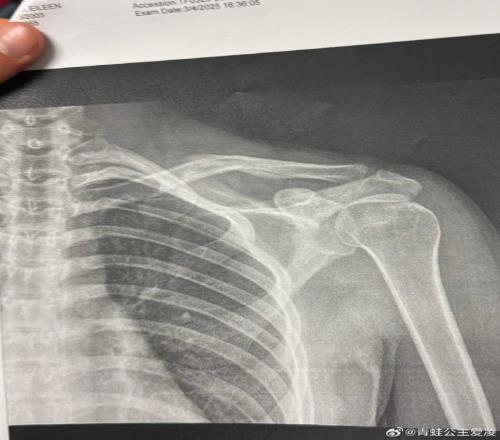

2025年3月9日,穀愛淩在社交網絡上發布了一張X光片。

但事實是,穀愛淩確實在這個奧運周期的最後衝刺階段不停經曆著傷病的折磨。2025年3月9日,穀愛淩在社交網絡上發布了一張X光片。圖片上,她右側鎖骨的裂縫清晰可見,配文隻有一個心碎的表情符號,而這僅僅是“職業生涯最艱難一年”的開始。